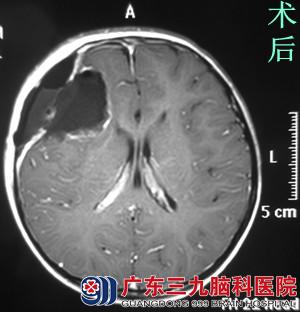

在朋友的联系下,小开的家人找到广东三九脑科医院 综合神经外科(神经外五科)的鲁明主任,鲁主任考虑小开年龄小,手术尽量避免功能障碍,术中唤醒麻醉及电生理监测。完善相关检查后,由鲁明主任主刀,在唤醒麻醉下行右额叶肿瘤切除术,术中导航引导,见灰白色肿瘤组织,质软,边界较清,唤醒患者,患者语言及肢体功能正常,显微镜下完整切除肿瘤,电生理监测未见明显皮层异常放电,术后小开未造成任何的功能障碍,手术顺利结束。术后小开经过专科治疗护理,顺利康复。术后病理结果:中枢神经系统节细胞神经瘤。

鲁明主任告诉小开妈妈:不是荔枝惹的祸,这次发病时偶然的机会发现的,所幸的是,在肿瘤还相对比较小时,早发现,早切除,没有让肿瘤继续长大酿成更严重的后果。